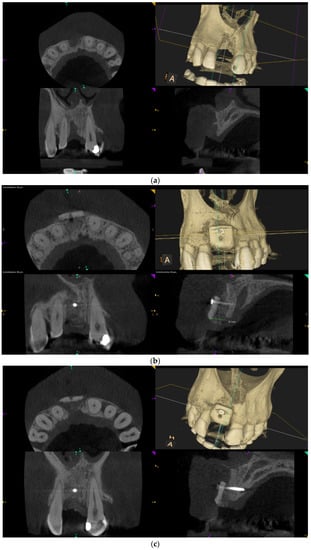

Over-contouring was defined as an over-augmentation of the alveolar process beyond the extent of the adjacent bone level (Figure 1). The reason for over-augmenting the alveolar process is often an anticipated shrinkage of the bone substitution material during the healing phase. Two patients were selected as examples to illustrate the term “over-contouring”. Patient 1 showed a Class III defect in the maxilla, and the alveolar ridge augmentation performed for correction was over-contoured (Figure 2). Patient 2 also showed a Class III defect in the maxilla, but the alveolar ridge augmentation performed for correction remained at the level of the surrounding bone (Figure 3).

Figure 2.

Clinical example of over-contouring. (a) Class III defect with pronounced vestibular deficit and minor vertical deficit. (b) Post-OP: Attachment of a cortico-cancellous allogeneic bone block. Vestibular over-contouring with the cortical plate and vertical over-contouring of the block can be seen. The block protrudes over the limbus alveolaris, i.e., over the bone border of the adjacent teeth. (c) After 5 months: the over-contoured portion of the cortical portion of the block was not resorbed, but part of the cancellous portion of the block was palatally resorbed away. (d) The over-contoured block penetrates the mucosa. The cortical portion is revealed.